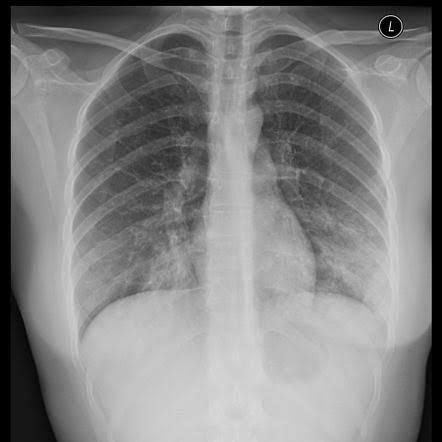

Atypical Pneumonia is a type of community acquired pneumonia which is caused by an organism that are not stained on gram stain and not culturable on standard blood agar. Most common organisms are Legionella pneumophilia, mycoplasma, Chlamydia and viral. Patient with the gradual onset of cough which is non-productive and associated with the extrapulmonary symptoms such as headache, mylagia and GI symptoms. On Chest x-ray it presents as bilateral interstitial infiltrates.